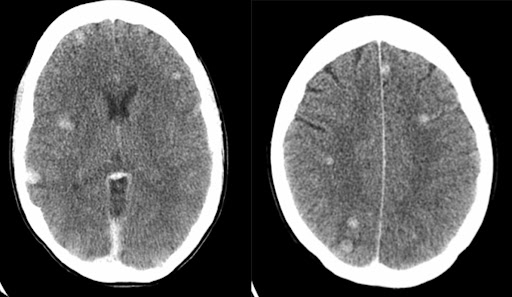

CyberKnife σε πολλαπλές εγκεφαλικές μεταστάσεις από καρκίνο του πνεύμονα

Μια πρόσφατη μελέτη περιγράφει την περίπτωση ενός 46χρονου άνδρα με καρκίνο του πνεύμονα και απειλητικές για τη ζωή μεταστάσεις στον εγκέφαλο. Ο ασθενής είχε διαγνωστεί με καρκίνο του πνεύμονα, με κλινικό στάδιο T2N0M1 (στάδιο IV). Έξι μήνες μετά την αρχική διάγνωση και τη σύμμορφη ακτινοθεραπεία του πνεύμονα σε συνδυασμό με τρεις κύκλους χημειοθεραπείας, η αξονική τομογραφία του εγκεφάλου αποκάλυψε εγκεφαλικές μεταστάσεις που ήταν διασκορπισμένες σε ολόκληρο τον εγκέφαλοΟ ασθενής υποβλήθηκε σε τρεις συνεδρίες με Cyberknife 22 Gy στις εγκεφαλικές μεταστάσεις. Μετά τη θεραπεία με CyberKnife η αξονική τομογραφία του εγκεφάλου αποκάλυψε ότι οι όγκοι είχαν εξαφανιστεί.